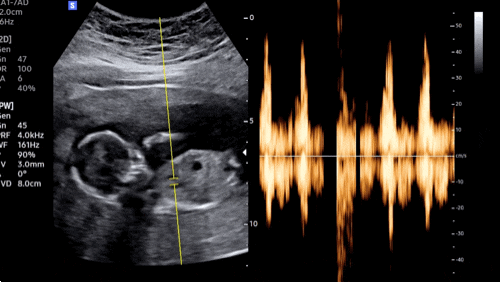

[임신 17주차] 증상, 에어링다운, 찢어지는 듯한 통증!

16주를 나름 무난히 보내서 따로 글을 쓰지 않았나본데..?..(글이 없음;;;) ?17주차 증상? 1. 17주 3...